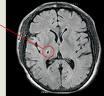

IMRISNV features a 3T MRI scanner and a bi-plane angiography system specifically designed to co-exist in the same suite. Patients with acute ischemic stroke transition seamlessly from MR imaging to intervention without moving from the table. During and after the intervention, new MR images can be taken to assess the effectiveness of the treatment. IMRISNV is designed to shorten transition time between imaging modalities, decrease the overall time for treatment and improve patient outcomes.